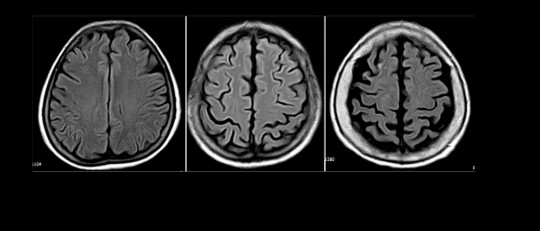

Lo primero que debemos tener en cuenta es que el cerebro de los niños no está completamente desarrollado ni a nivel estructural ni a nivel funcional. De hecho, el proceso de maduración cerebral continúa hasta los 20 o 25 años.

Esto quiere decir que puede haber grandes diferencias en el desarrollo entre determinadas áreas y, a decir verdad, así es. Por ejemplo, mientras el “cerebro emocional” (sistema límbico) está bastante desarrollado ya desde el nacimiento, el “cerebro racional” (corteza prefrontal) apenas funciona durante los primeros años de vida.

Esto implica que los niños pueden sentir emociones muy intensamente desde edades muy tempranas, pero no tienen herramientas para regular dichas emociones porque el autocontrol, la reflexión, la lógica y la regulación emocional dependen de áreas como la corteza prefrontal, que se maduran con el tiempo.

Es decir, las criaturas experimentan las emociones en su cuerpo y, como consecuencia, reaccionan. Actúan sus emociones. Podríamos decir que son una especie de coche muy rápido al que los frenos no le funcionan del todo bien. Y es crucial comprender que esto es algo madurativo, que no es algo que hagan a propósito o con intención de fastidiar a nadie.